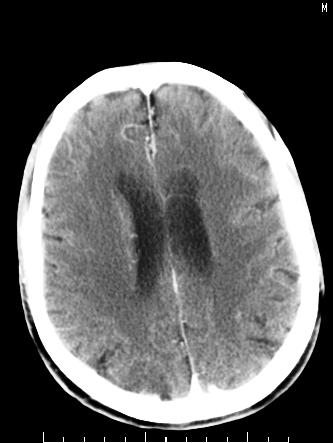

m/50,头昏头痛1月,近3天感觉左半肢体活动不利,自述半年前呈患肺tb,腰穿脑脊液未见特殊改变。现做头颅ct请大家会诊。

ct值?是囊变?梗塞软化灶形成

考虑:1.结核脓肿,2.星形胶质瘤,但脑积液正常,这考虑肿瘤的可能性大些.期待结果

首先考虑肿瘤性病变,星形细胞瘤可能性大,不排外转移瘤。建议mri。

请大家结合临床表现看一下 左侧肢体的症状是脑干 还是其他的问题 另外结核感染脑脊液应该有问题 所以应该考虑肿瘤性病变